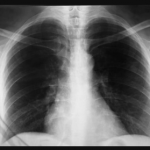

PULMOLOG MIODRAG OTKRIO KOJI JE NAJBOLJI LIJEK ZA UPALU PLUĆA: Ove 2 stvari zajedno...

Značajni zdravstveni problemi poput upale pluća i kroničnog kašlja mogu ozbiljno utjecati na kvalitetu života pojedinca. Nevolja koja proizlazi iz simptoma uključujući bol u...